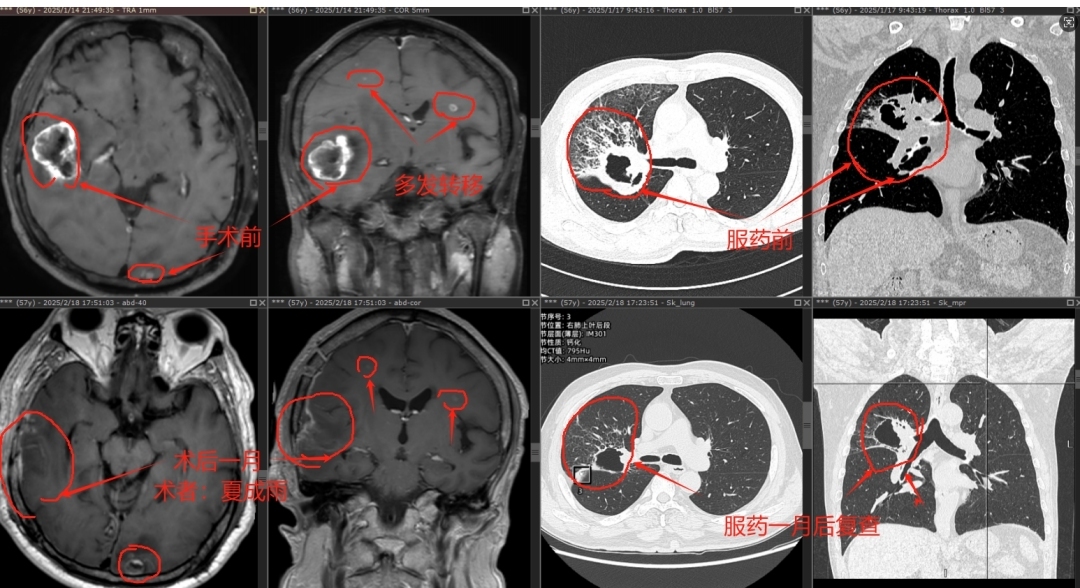

56岁的坚叔(化名)查出肺癌时已伴有颅内多发转移,不适合肺癌切除手术,其中右颞叶转移瘤最大径足有3.75厘米,肿瘤周围大面积脑水肿,硬生生地将大脑中线结构挤到移了位,颅内压力明显增高,出现无法缓解的头晕、头痛等症状。

“在这种情况下,如果贸然放疗,对肿瘤的‘攻击’不一定会有效,而脑水肿必然会加重,很有可能闯不过放疗后脑水肿加重的难关,如果发生脑疝,那就更危险了。”广州医科大学附属第一医院神经外科学科主任、主任医师夏成雨仔细为坚叔评估病情后,决定先为他施行手术切除右颞叶转移瘤。术后,坚叔的颅内高压“警报”症状“头痛头晕恶心”逐渐解除,术后一月复查原本被肿瘤和大面积脑水肿推挤移位的脑中线结构逐渐归位了,肿瘤周围的脑水肿也显著消退了。

坚叔治疗前后检查结果对比。

术后,结合病理和基因检测分析,医生为坚叔找到了合适的靶向药物。经过一段时间的靶向治疗,坚叔肺部肿块体积显著缩小了。